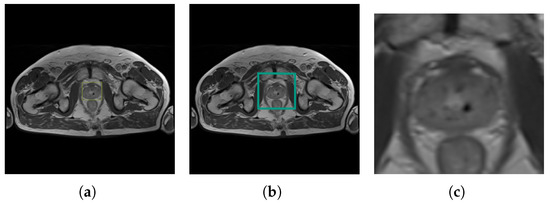

The predicted prostate image was subjected to additional processing, as presented in Figure 7. The object detected by the YOLOv4 with the bounding box label enabled further image processing. Subsequently, an additional 15 px of padding was added. The framed part of the image had been cut out and resized to 256 × 256 pixels. The cropped image was prepared in order to become the input for the U-Net Segmentation Neural Network. The complete post-processing workflow is visualized in Figure 4.

Figure 7.

Post-processing of prostate detection image: (a) detection bounding box, (b) predicted bounding box, and (c) cropped image (U-Net input).

The YOLOv4 is an intermediate stage for segmentation carried out by the U-Net neural network. In this paper, the purpose of YOLOv4 is to filter areas where prostate cancer can initially be found. Figure 4 presents the created research workflow.

Figure 4.

Post-processing workflow for prostate detection image. Legend starting from left: input image in N × N size; YOLOv4 convolutional neural network; prostate detection output with yellow bounding box; prostate detection output with enlarged turquoise bounding box (15 px padding); cropped prostate detection output and resized into 256 × 256 px as U-Net input; U-Net convolutional neural network to segment prostate.